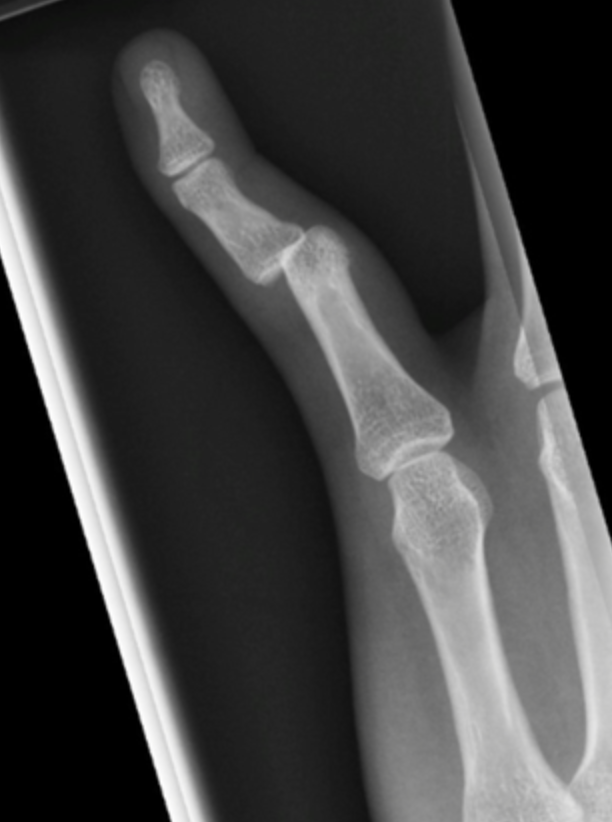

Finger Dislocations

Additional lateral dislocations

PIP dislocationPIP dislocationPIP dislocation